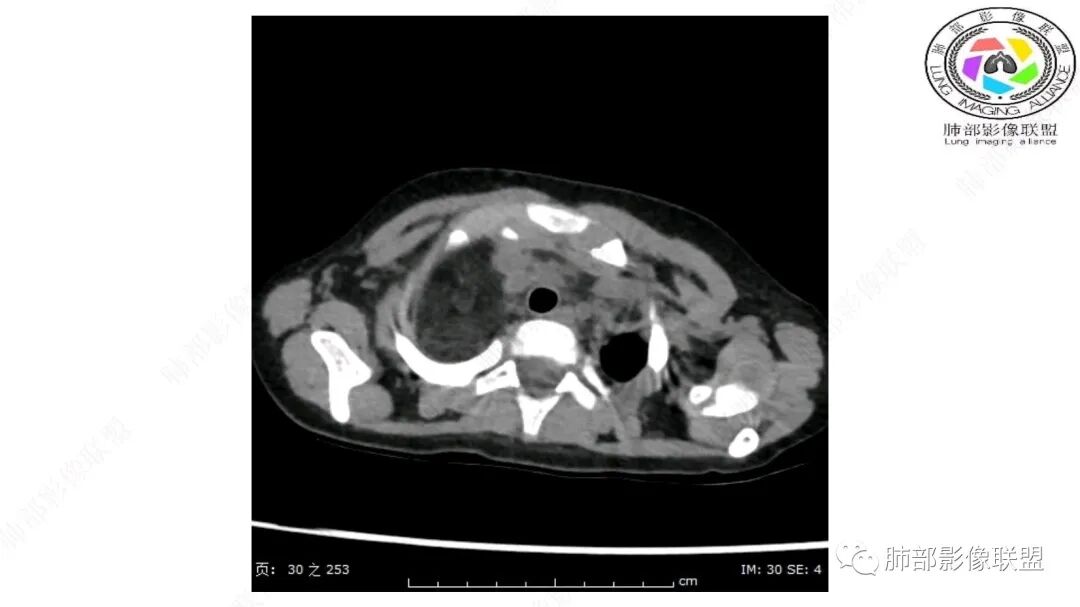

第一个问题:定位:肺内?纵隔?

病灶属于交界区,主体位于肺内,占位效应明显,前方突入胸壁,胸腺受压变形,胸膜显示欠清楚;病灶包绕上叶肺动脉;似乎有体动脉供血。符合肺内的点:包绕上叶肺动脉分支;符合纵隔的点:前方似乎突入胸壁,与胸腺关系比较密切,但是与上腔静脉的关系提示病灶不支持纵隔来源,前纵隔的常规会将上腔静脉受压后移、外移,这是不符合的。

从这个角度符合肺内的,有一点不太踏实的是:似乎突入前胸壁。

手术记录:见右肺上叶肿物,肿物与右肺上叶关系密切。与纵隔无粘连,逐步分离肿物,见肿物大小约6cm*5cm,边界清楚,于右肺上叶粘连,边界清楚,肿物包绕右肺上叶血管及支气管。超声刀逐步游离肿物,完整切除肿物,右肺上叶肺组织无破溃,表面无出血。